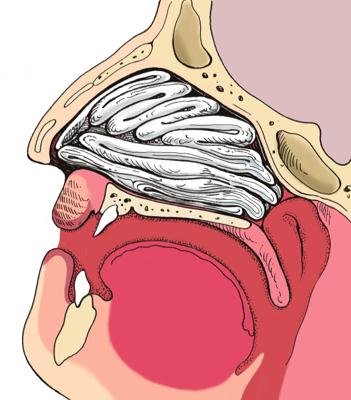

Anatomie-Physiologie du nez et des sinus : comment sont faits et fonctionnent le nez et les sinus.

Causes anatomiques – déviation du septum ou hypertrophie des cornets de votre nez

La septoplastie associée à une turbinoplastie – aide à supprimer les difficultés respiratoires causées par une déviation du septum et l'hypertrophie des cornets de votre nez.

Une septoplastie électrochirurgicale est effectuée par un otorhinolaryngologiste (ORL), médecin spécialiste des pathologies de l'oreille, du nez et de la gorge. Vous et votre ORL

déterminerez si une septoplastie électrochirurgicale associée à une turbinoplastie est le meilleur traitement chirurgical pour votre infection chronique des sinus

votre état. Pendant l'opération, votre ORL introduit un tube fin appelé endoscope dans votre nez. Ce tube est muni à son extrémité d'une minuscule caméra et d'un dispositif lumineux, ce qui permet au chirurgien de visualiser votre septum et vos cornets. De petits instruments chirurgicaux sont amenés jusqu'au site du problème.

Avec ces instruments, votre chirurgien corrige la déviation de votre septum et réduit le volume des cornets hypertrophiés. Cette opération dégage votre nez pour vous aider à respirer plus librement et améliore le drainage.